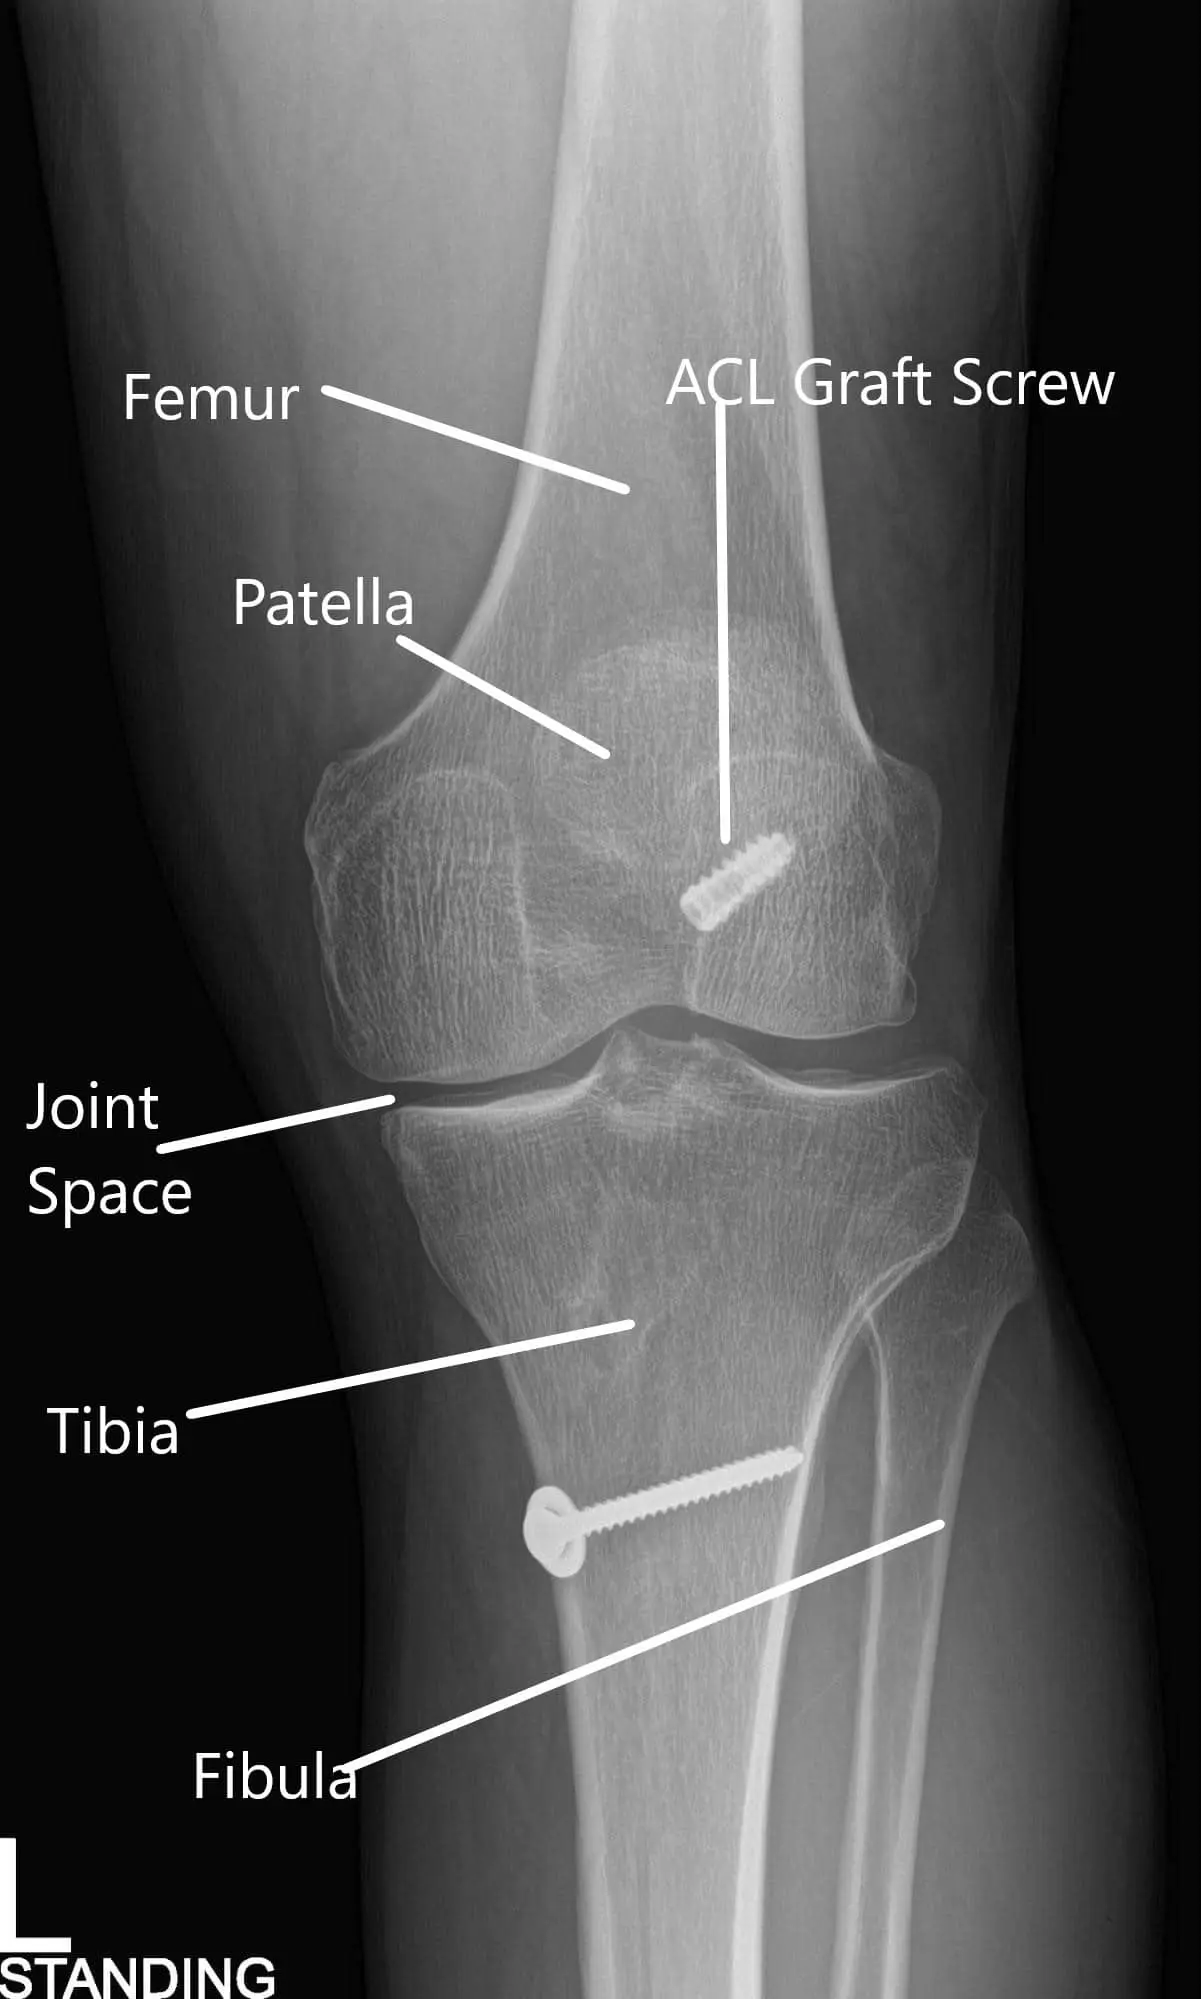

X-ray of the left knee in AP and Lateral views.

An X-ray of the left kee suggested a moderate narrowing of the medial joint compartment and status post ACL reconstruction.